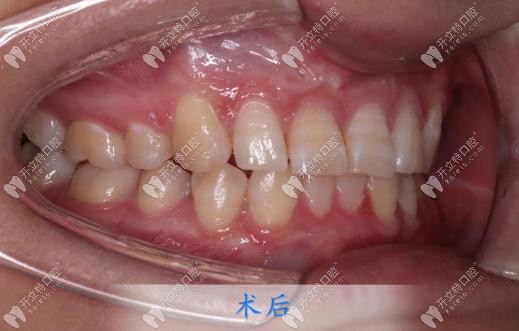

跑偏了,取下牙套后,牙齒的情況已經(jīng)全部改善了。但更讓我開心的是我的下巴,之前因?yàn)樽彀蛯?dǎo)致下巴不明顯,矯正后下巴竟然有了,顏值也改變了好多,朋友見我都說我變好看了,但是又說不出來哪里變了!

都說牙齒矯正做好了堪比整容,我以前是真不信這句話的,直到自己親身經(jīng)歷,還是想給小伙伴們提個(gè)醒:找個(gè)認(rèn)真且負(fù)責(zé)的正畸醫(yī)生,真的可以省去好多麻煩!